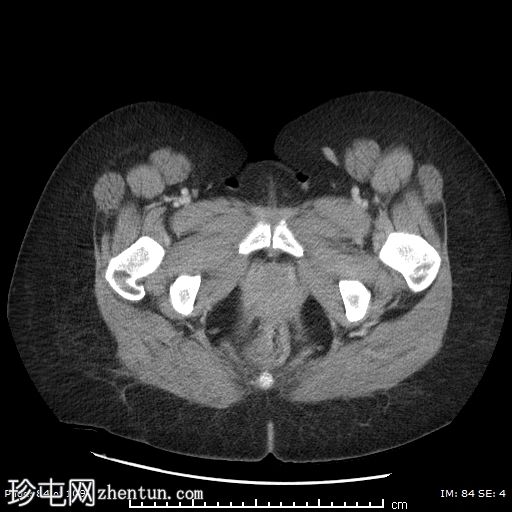

轴位增强扫描(门静脉期)

左侧附件区可见一巨大囊性病变,大小约9 x 12 cm,主要呈液体密度,囊壁光滑薄。

邻近一复杂囊性成分,向中线延伸,大小约10 x 9 cm,内部可见分隔及不均匀液体密度,提示内容物可能为出血性或部分复杂性。

左侧附件区可见一边界清晰的卵圆形低密度肿块,大小约4 x 4 cm,囊壁厚,内部为软组织、脂肪和液体混合密度,符合成熟囊性畸胎瘤(皮样囊肿)的影像学表现。

左侧附件血管蒂扭转,形成血管和软组织呈漩涡状排列,高度提示卵巢扭转。

可见轻度卵巢周围脂肪条索状改变和少量邻近盆腔积液,可能为继发性充血和水肿。

由于左侧附件增大的组织结构压迫,子宫向右侧移位。

右侧附件未见异常。

阑尾大小和直径正常,无急性阑尾炎的证据。